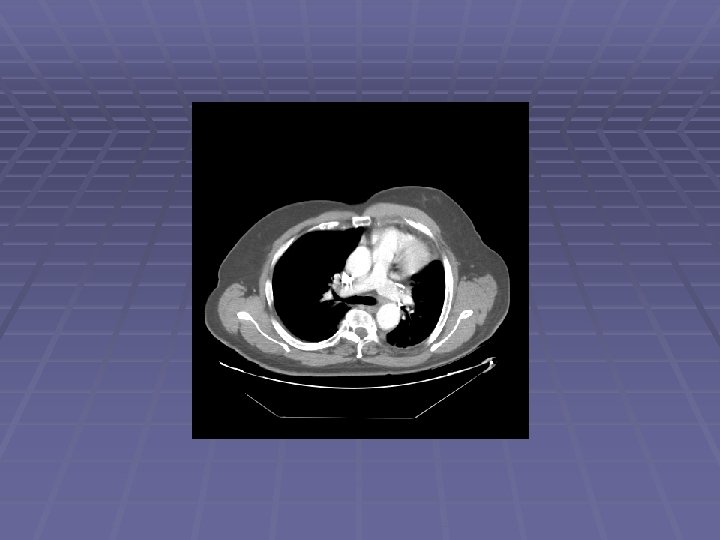

Patient CE 69 y. o. man with h/o non-small cell lung cancer s/p LUL resection in 2006 who is referred after a chest CT showed new mediastinal lymphadenopathy EUS/FNA scheduled to evaluate for recurrent disease

Endosonographic Evaluation EUS Suspicious lymph nodes in the aortopulmonary window, sized 6 -11 mm Suspicious lymph nodes in the subcarinal space, sized 6 -12 mm FNA performed